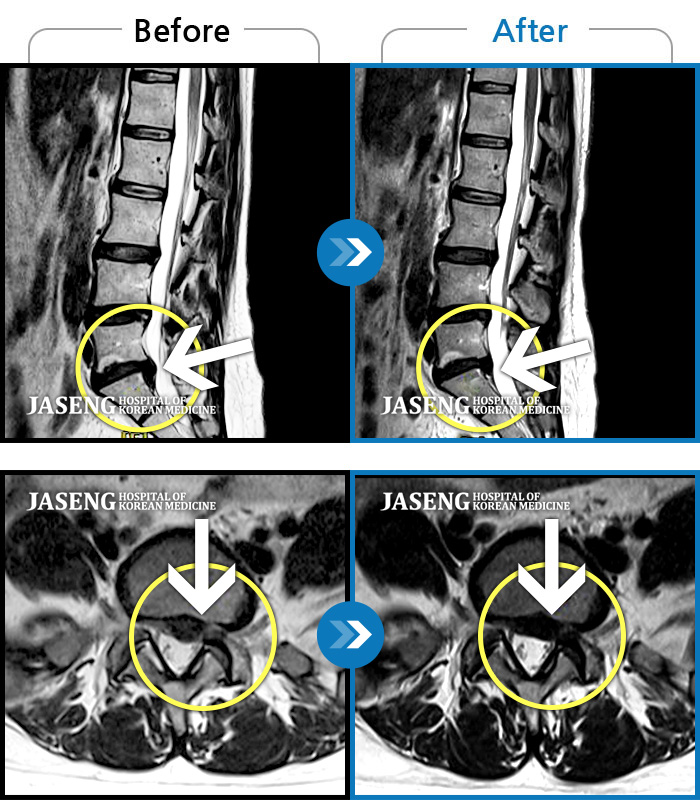

Before

After

환자에게 사전 동의를 받아 동일 조건에서 촬영되었습니다.

개인에 따라 치료 후 부작용이 발생할 수 있으니 의료진과 상담 후 치료를 진행하시기 바랍니다.

좌측 허리 통증으로 허리를 반듯이 펴고 서있기 힘들어 내원하셨습니다.